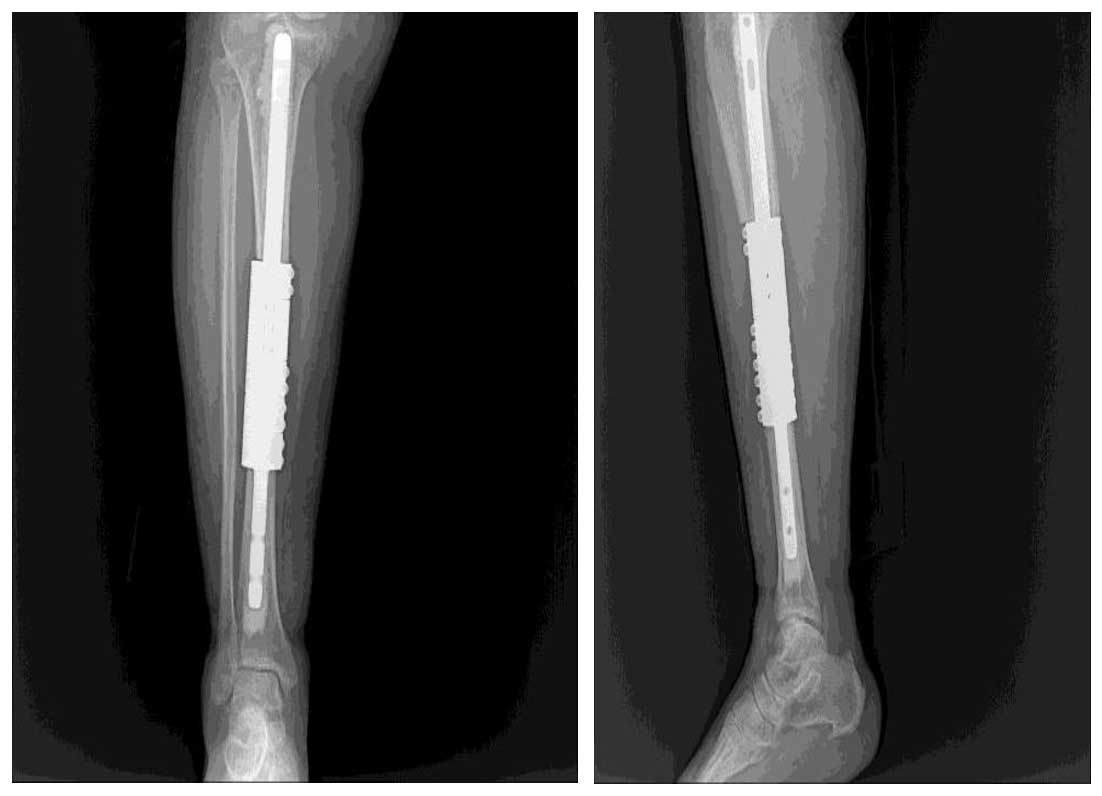

Ameliyat Sonrası: çıkarılan tümörlü kemiğin yerine çimentolu tümör protezi uygulanımı.